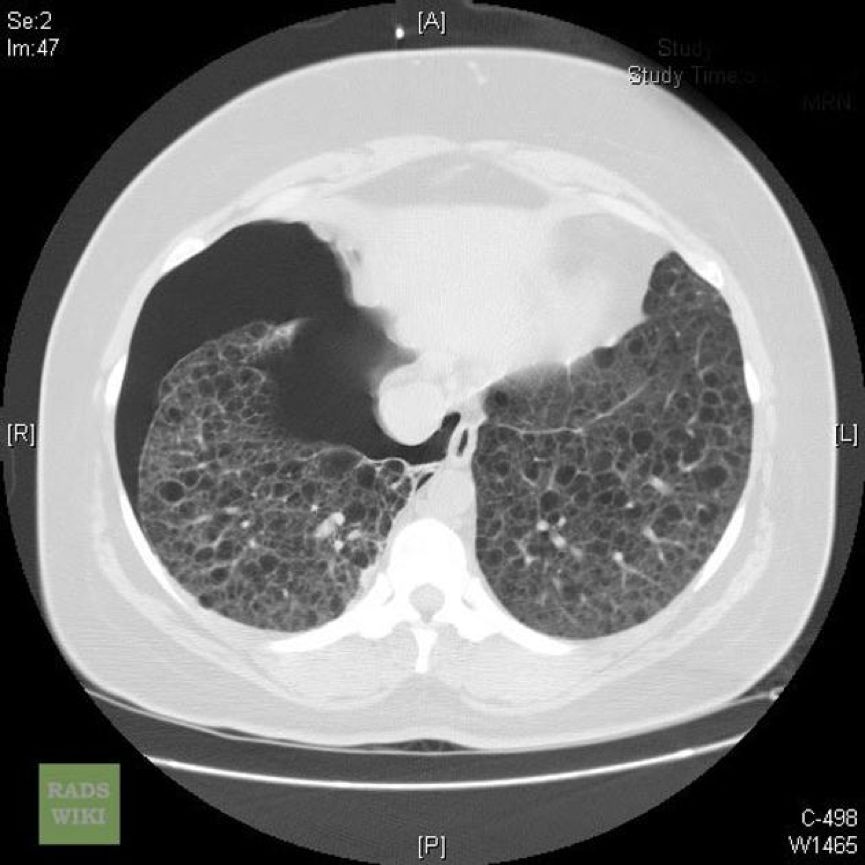

外院肺功能检查提示:阻塞性通气功能障碍。HRCT显示双肺弥漫性分布类圆形薄壁囊状阴影,囊壁较光滑,囊腔大小不等,多数在2~10 mm之间,右侧胸腔内见气体影。纵隔结构清楚,未见肿大淋巴结。

常规CT表现为两肺密度减低,体积增大,呈肺气肿样改变。HRCT对本病的早期诊断及病情发展的监测有重要意义,其特征性改变为两肺广泛弥漫性分布的薄壁小囊状病变,两侧对称,无上中下肺野的区别,也无中央性与周围性的分布差异。囊腔直径为2~30 mm,大多数直径小于10 mm,囊壁厚度多小于2 mm。